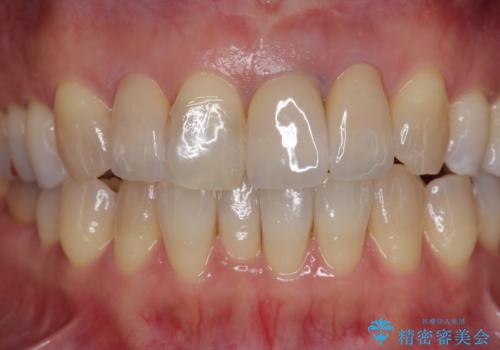

装着されているセラミッククラウンを除去したのち、現在の歯ぐきのラインにしっかりと合う精度の高いオールセラミッククラウンを作製していきます。

周囲の歯に調和したセラミッククラウンを作製し、審美性を大幅に向上させることができました。